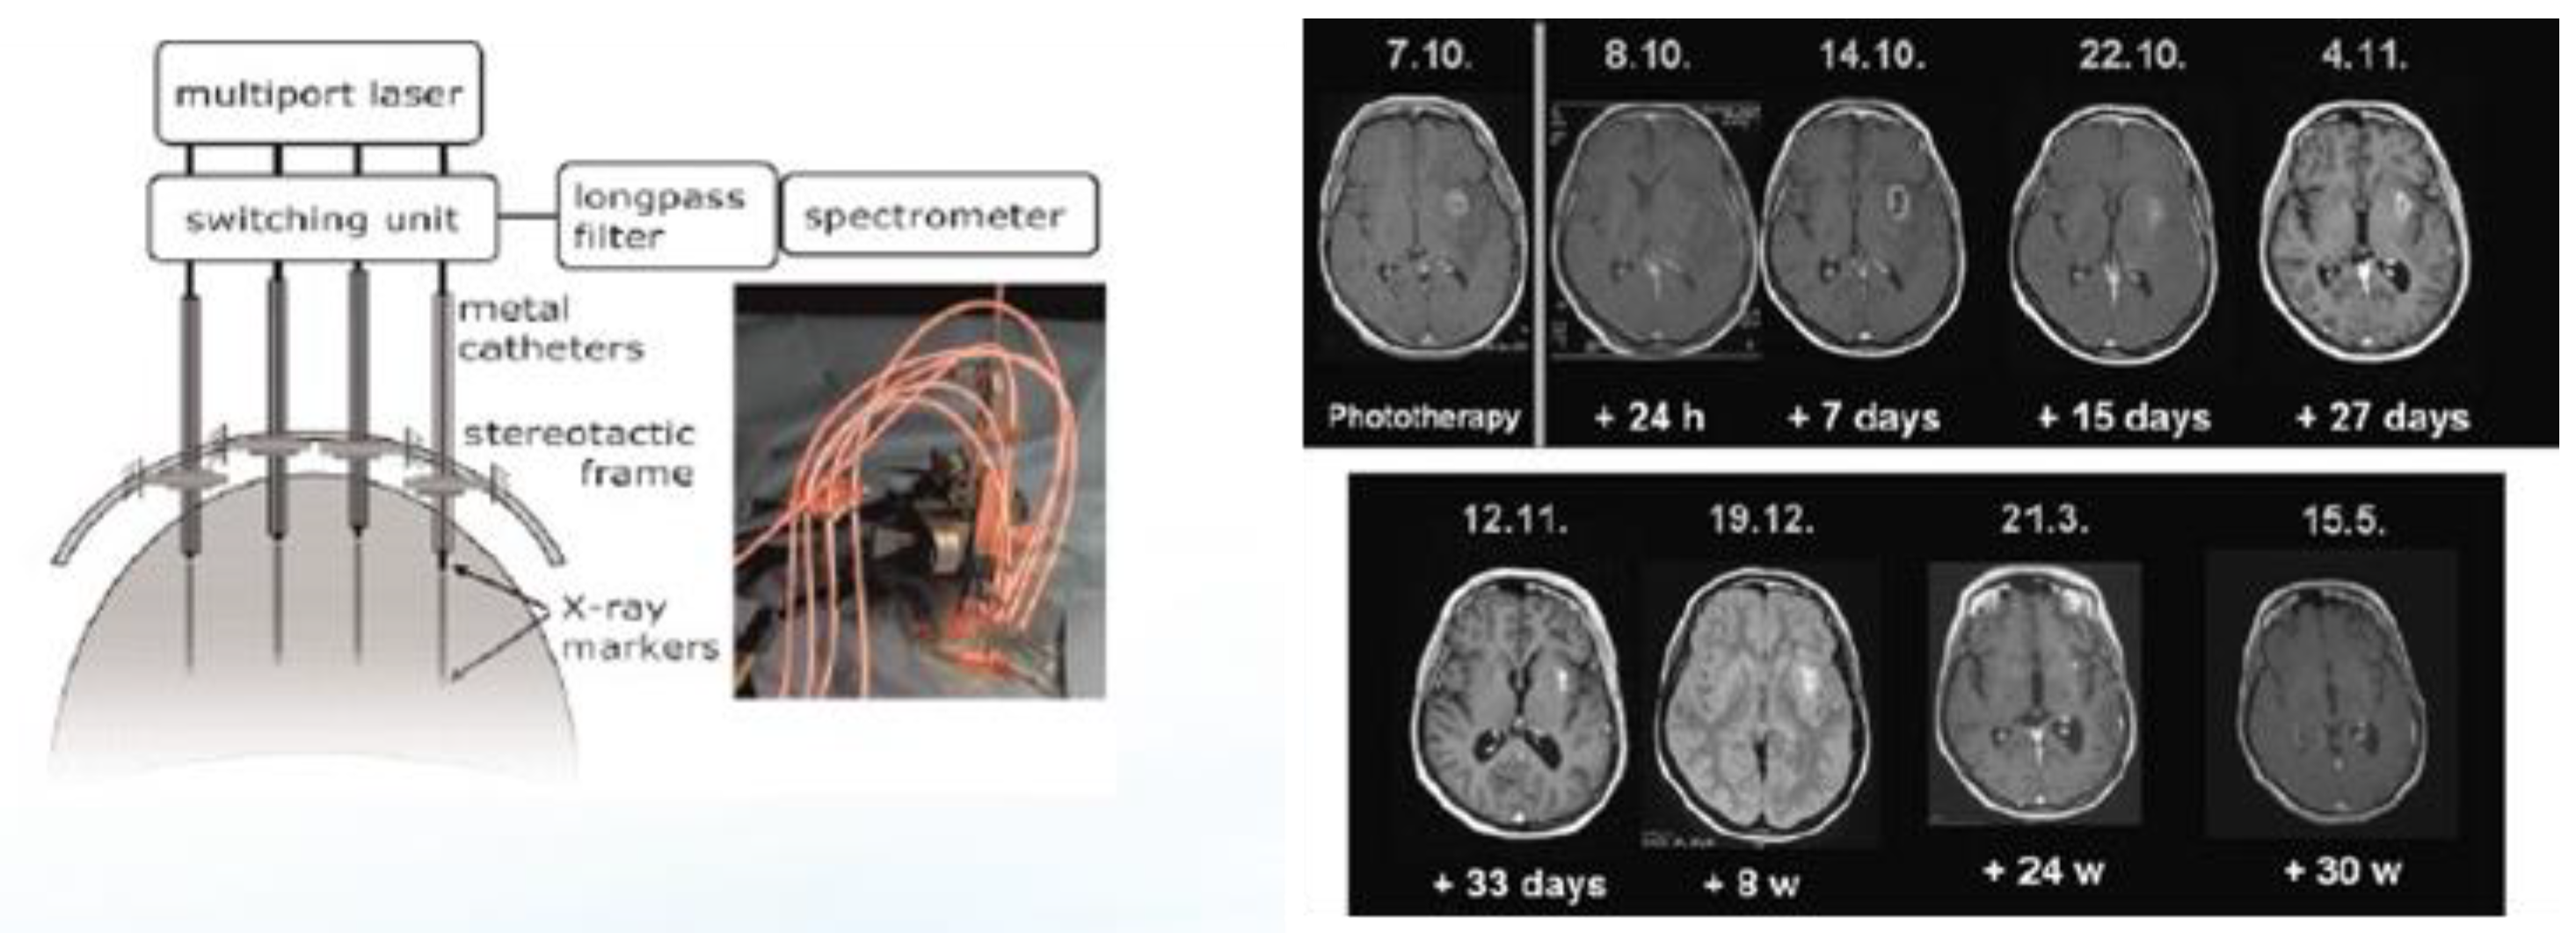

2.2. Interstitial ALA PDT (iPDT) for the Treatment of Recurrent Glioblastomas (rGBMs)

- Beck, T.J.; Kreth, F.W.; Beyer, W.; Mehrkens, J.H.; Obermeier, A.; Stepp, H.; Stummer, W.; Baumgartner, R. Interstitial photodynamic therapy of nonresectable malignant glioma recurrences using 5-aminolevulinic acid induced protoporphyrin IX. Lasers Surg. Med. 2007, 39, 386–393. [Google Scholar] [CrossRef] [PubMed]

- Johansson, A.; Faber, F.; Kniebühler, G.; Stepp, H.; Sroka, R.; Egensperger, R.; Beyer, W.; Kreth, F. Protoporphyrin IX fluorescence and photo-bleaching during interstitial photodynamic therapy of malignant gliomas for early treatment prognosis. Lasers Surg. Med. 2013, 45, 225–234. [Google Scholar] [CrossRef] [PubMed]

- Lietke, S.; Schmutzer, M.; Schwartz, C.; Weller, J.; Siller, S.; Aumiller, M.; Heckl, C.; Forbrig, R.; Niyazi, M.; Egensperger, R.; et al. Interstitial Photodynamic Therapy Using 5-ALA for Malignant Glioma Recurrences. Cancers 2021, 13, 1767. [Google Scholar] [CrossRef] [PubMed]